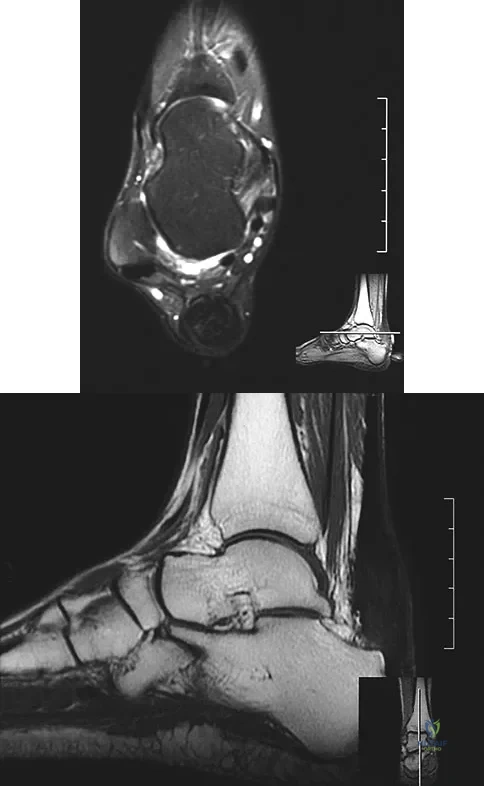

A 35-year-old female runner reports progressive vague aching pain involving her midfoot. Her pain is most notable when running. She denies specific injury. Examination reveals minimal swelling and localized tenderness over the dorsal medial midfoot and navicular. Radiographs and an MRI scan are shown in Figures 37a through 37c. What is the most appropriate management?